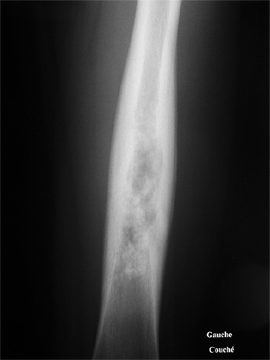

Pathologies infectieuses osseuses

Il s'agit des ostéomyélites sub-aigues et chroniques.

Ce sont des infections

bactériennes des os qui se développent doucement, sans

provoquer des signes généraux (ni fièvre, ni frisson,

ni altération de l'état général) et qui

s'accompagnent de douleurs.